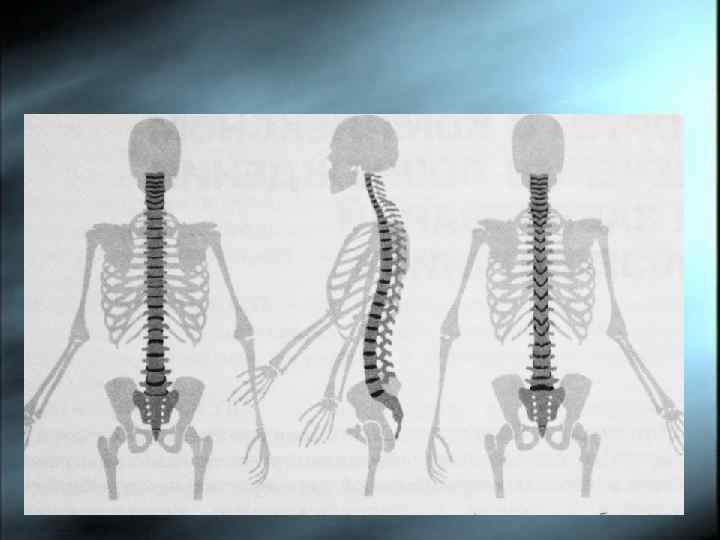

Виды искривлений позвоночника Плоская спина, кифоз, гиперлордоз, норма Виды искривлений позвоночника Плоская спина, кифоз, гиперлордоз, норма